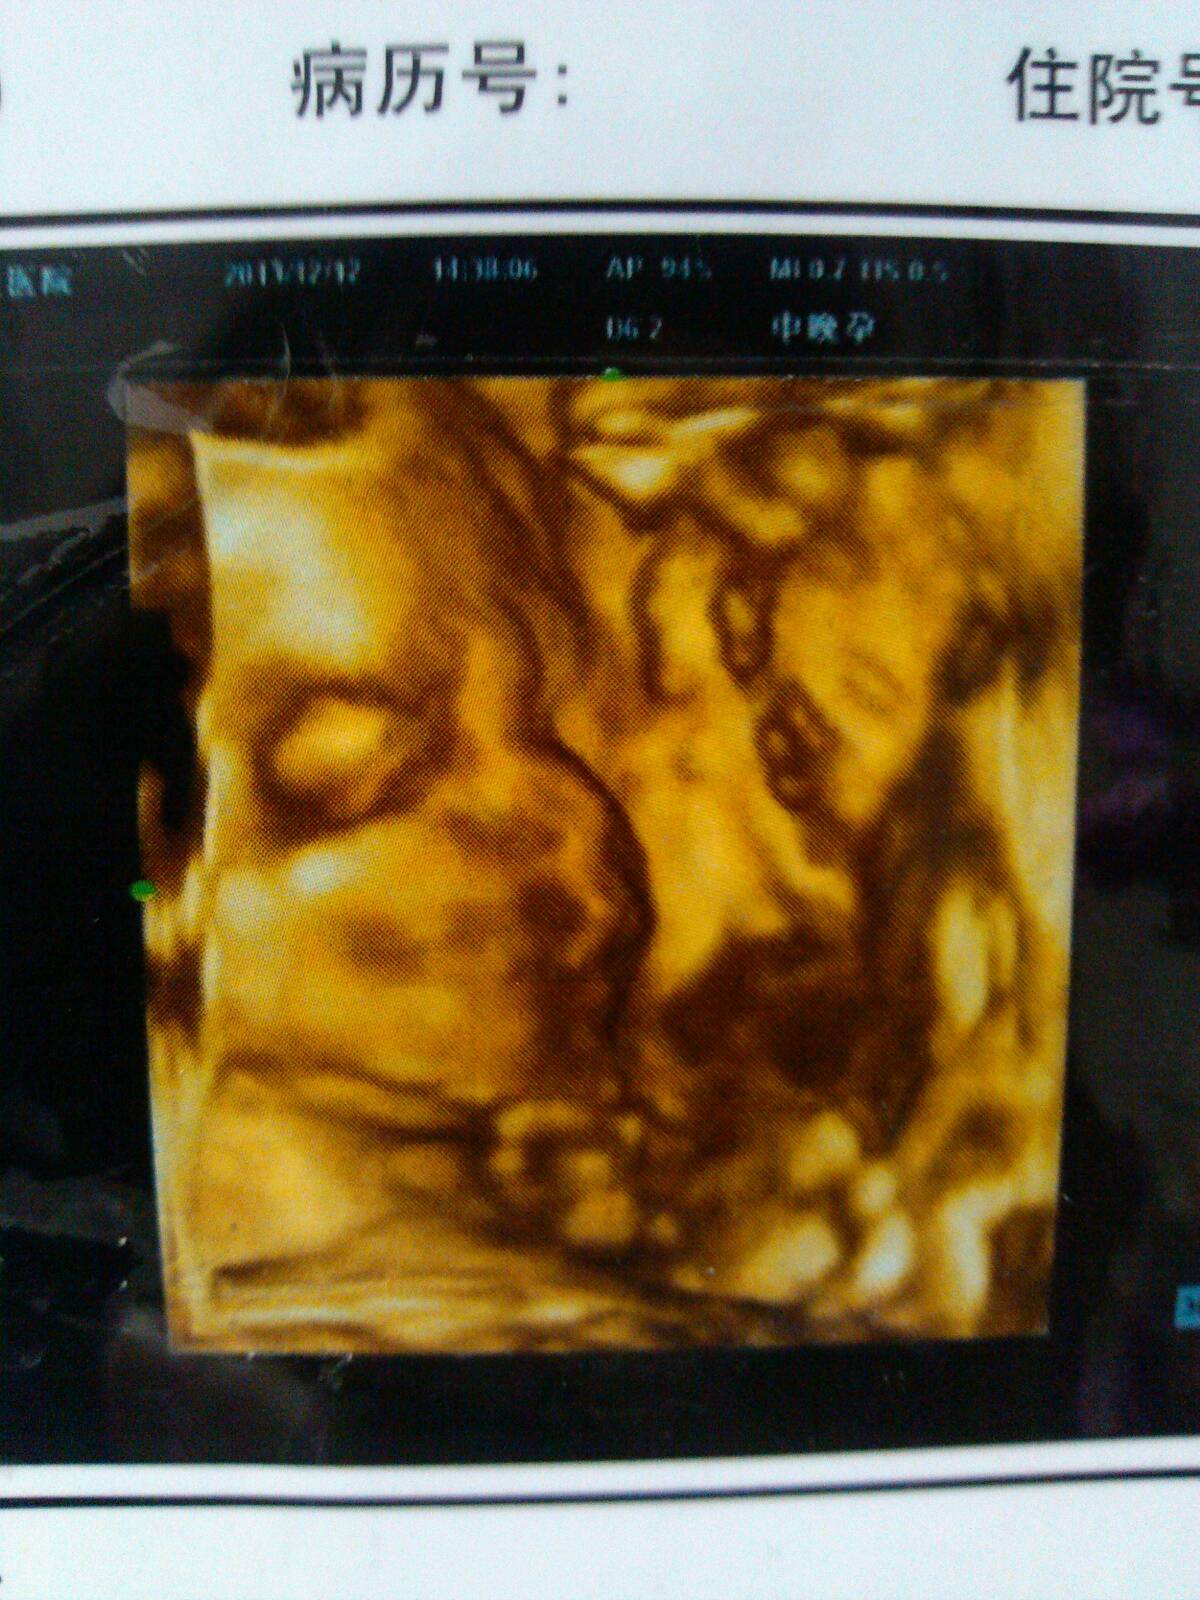

请会看思维的帮忙看看,宝宝脸上的黑点是什么,不会是皮肤病吧 点击展开 母婴用户142397863 2014-01-16 10:18 为您推荐: 其他回答 病情分析: 你好,根据你所描述的情况,这个只是影像学的现象,不是皮肤病的,不用过于担心。 指导意见: 你好,根据你所描述的情况,平时注意休息,加强营养,定期产检。 匿名用户 2014-01-16 10:21 相关问题 十个月的宝宝脸上毛孔里有黑点是皮肤病吗 宝宝满月的时候发现的,现在3个月了还扩张了!想知道这是什么皮肤病懂的帮忙看看! 小孩脸上每年夏天起皮肤病